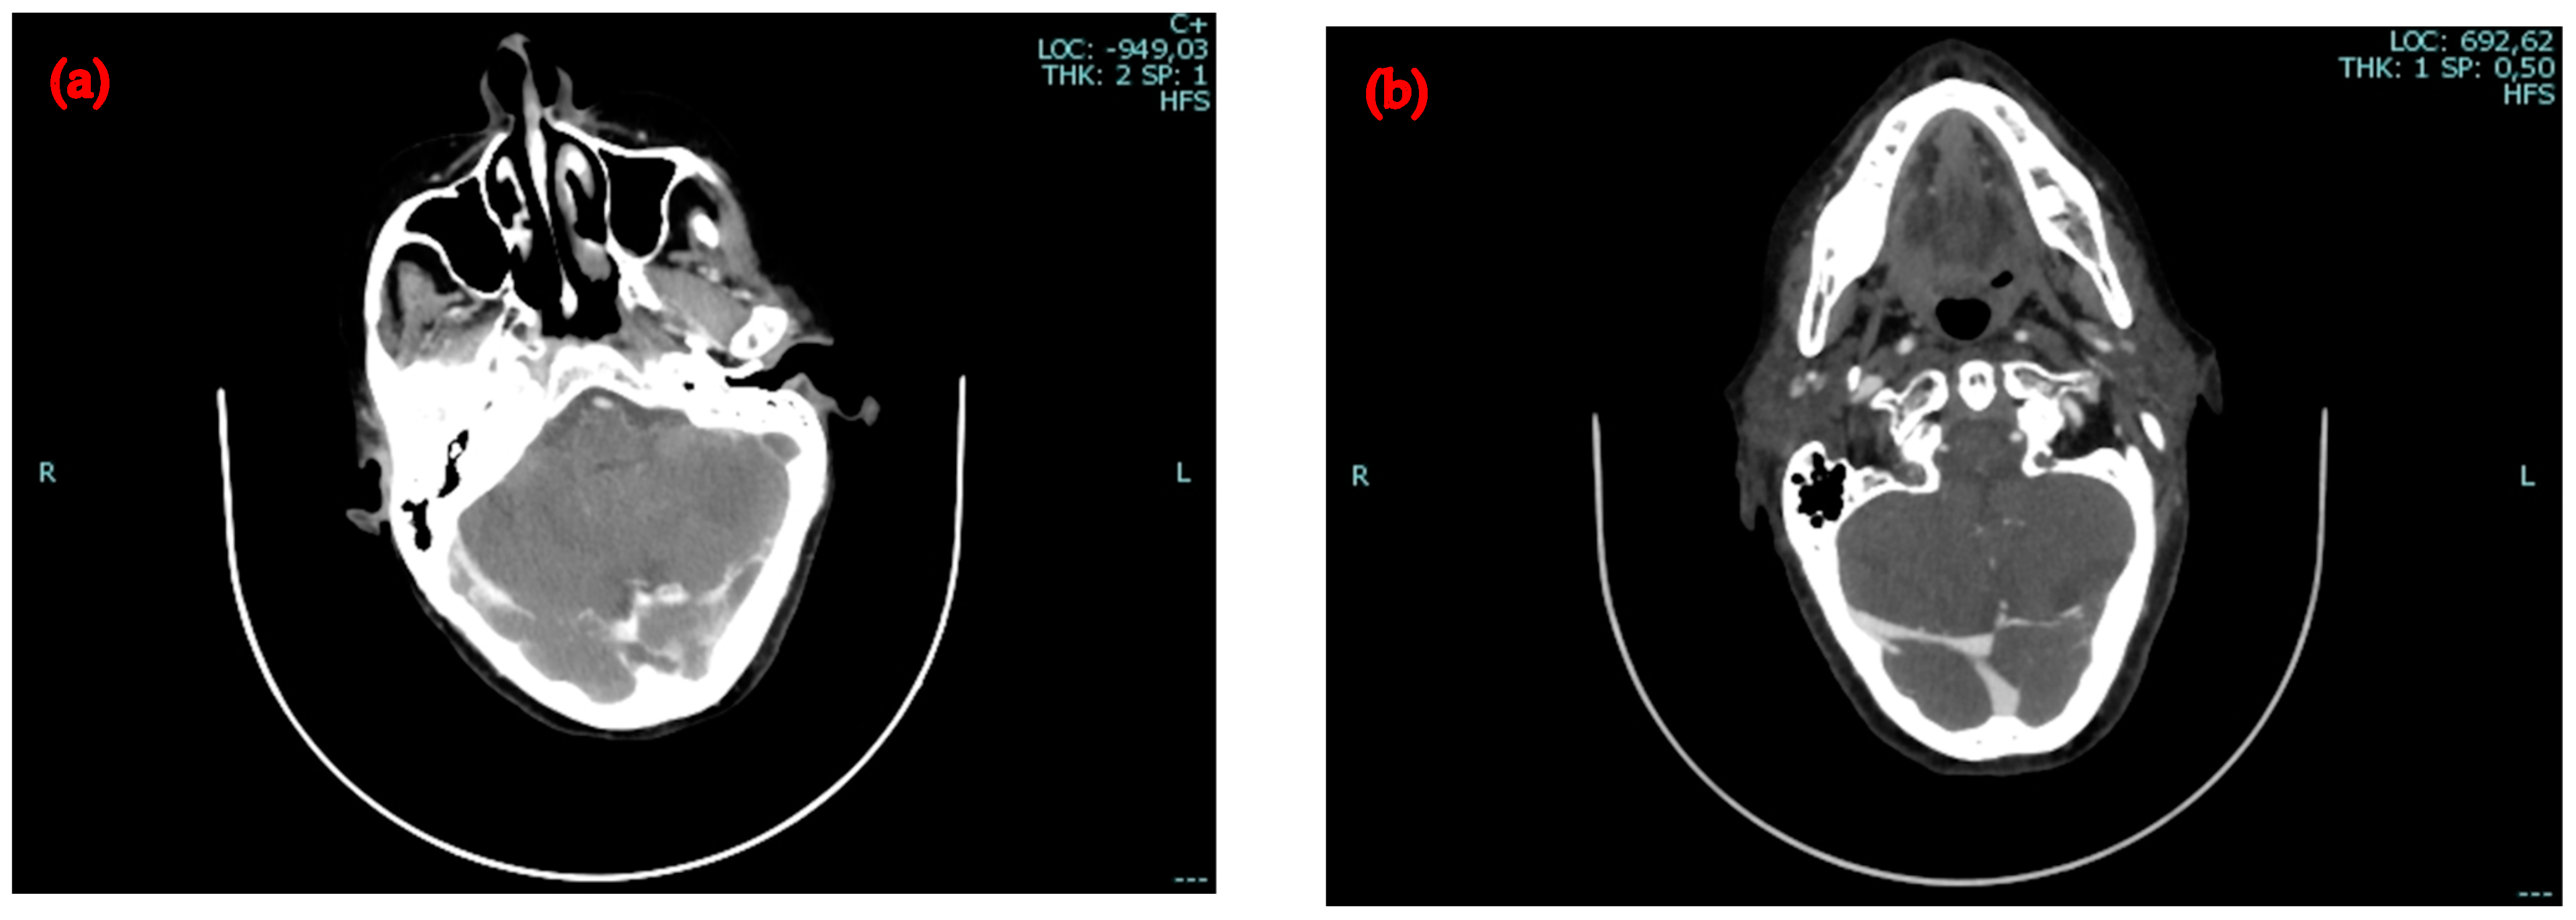

2.2. Second Admission to the Same Hospital

2.3. Admission to the Infectious Diseases Unit of Our University Hospital

4.4. Venous Thromboses and Other Complications